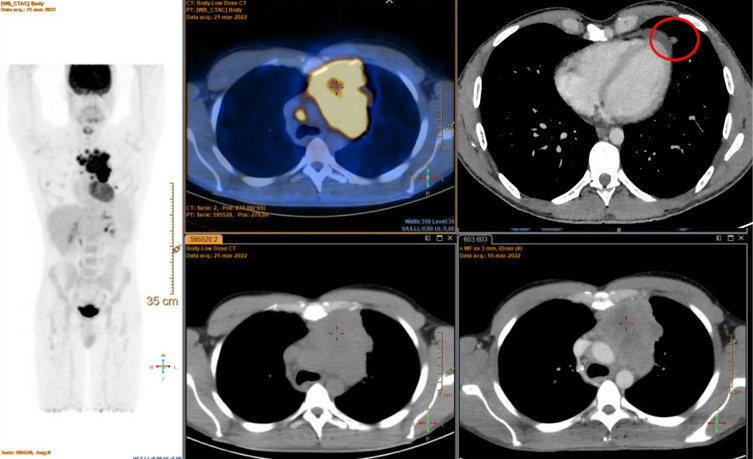

Case description: We present the case of a 31-year-old male diagnosed with stage IVA squamous TC. Following disease progression after first-line chemotherapy with paclitaxel, carboplatin, and ramucirumab as part of the RELEVENT phase II trial, PD-L1 assessment revealed an 85% expression, leading to the initiation of off-label pembrolizumab (200 mg every 3 weeks). The patient subsequently developed oligoprogression with local sternal infiltration, prompting the addition of radiotherapy (10×3 Gy) alongside continued pembrolizumab. Over the following months, imaging demonstrated progressive response to treatment, culminating in a near-complete metabolic response. A residual mediastinal lesion was later surgically resected, revealing no viable tumor cells, indicative of a complete pathological response. Nine months after surgery, the patient is disease-free, with no reported immune-related adverse events.